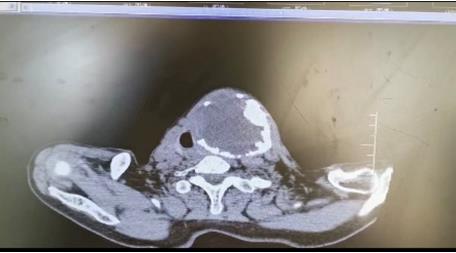

患者朱女士,68岁,颈部包块呈进行性增大50年,来院后彩超及CT提示左侧甲状腺肿瘤已经超过10公分并边缘钙化,气管移位较明显,肿瘤较大属于罕见,不仅给患者造成心理阴影,还影响了正常生活,偶有憋闷不适,进食较大食物感哽咽不适。流动医院下乡义诊时,发现包块已经很大了,影响到颈部的活动及饮食。医生与患者及家属沟通讲解病情,表示我们三甲医院能治疗。最后患者及家属抱着试一试的态度来到延安大学咸阳医院。

因逐渐长大的颈部严重影响饮食及活动,长达50年的折磨,患者身体很瘦、体质差。甲状腺肿瘤,瘤体大,手术创面较大,损伤喉返神经及甲状旁腺风险高,术后可能出现声音嘶哑及低钙抽搐等严重并发症。同时瘤体长期对气管的压迫,致术后可能出现气管软化而发生致命性并发症。

经过普外二科赵建辉主治医师及他们的团队与麻醉科讨论研究,认真分析颈部的解剖结构。确定最优手术方案。于2022年1月14日上午在全身麻醉下行左侧甲状腺大部分切除+喉返神经探查术,手术历时1.5小时,顺利结束,出血量较少,术中快速冰冻为结节性甲状腺肿。考虑到创面较大,术中放一条引流创腔管,较好的保护了喉返喉上神经及甲状旁腺,手术成功。